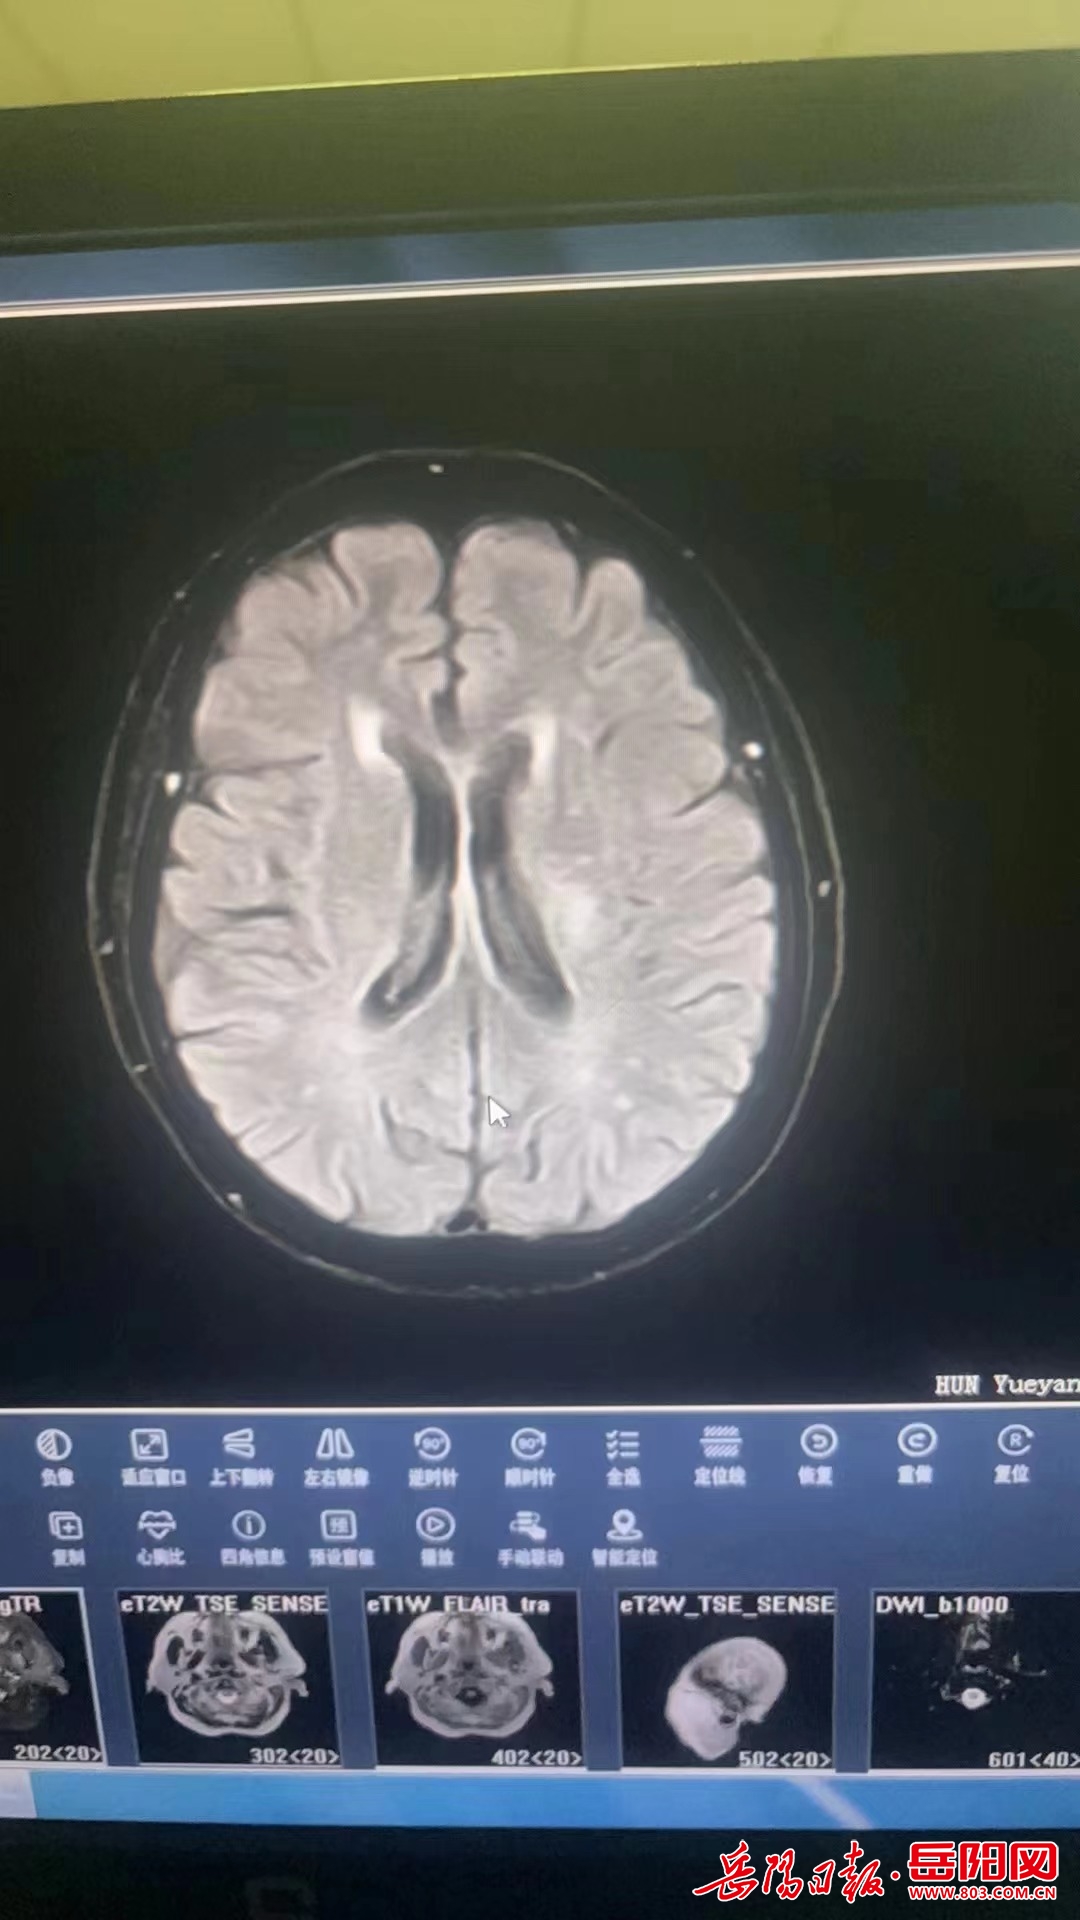

岳阳楼区人民医院开展急性缺血性脑卒中阿替普酶

图片尺寸1080x1920